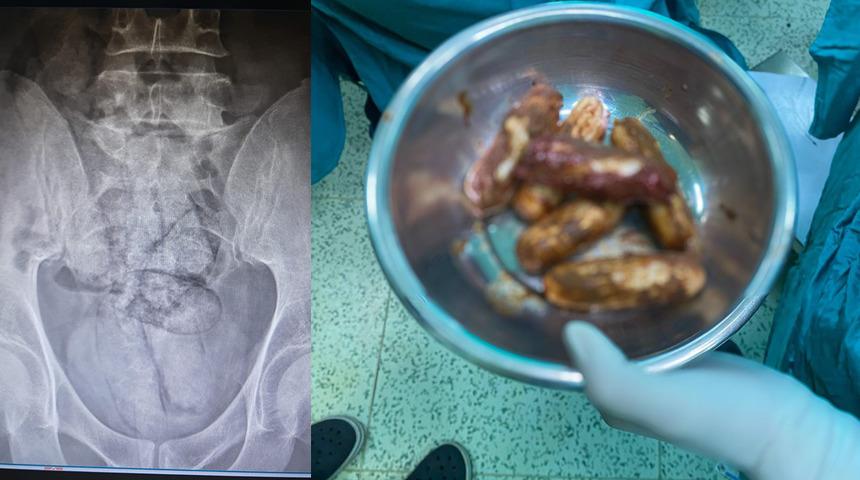

İl jandarma ekipleri, takip ettikleri İran uyruklu şüpheliyi dün saat 02.00 sıralarında Çayağzı Mahallesi’nde durdurdu. Üzerinde yapılan aramada herhangi bir olumsuzluğa rastlanmayan F.R., detaylı kontrol için hastaneye götürüldü. Artvin Devlet Hastanesi’nde tomografisi çekilen şüphelinin bağırsaklarında 10 paket halinde uyuşturucu madde taşıdığı belirlendi.

Şüphelinin hayati tehlike oluşturabilecek şekilde sakladığı paketler, cerrahi müdahaleyle çıkarıldı. İncelemede paketlerin içinde toplam 350 gram metamfetamin olduğu tespit edildi.